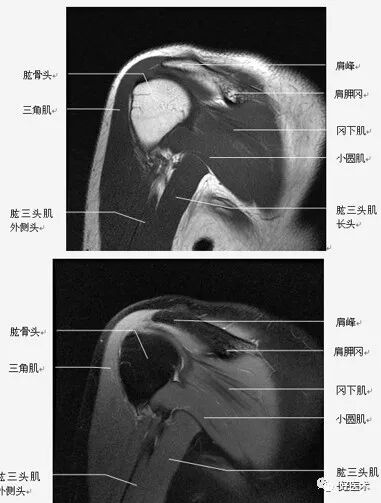

(2)肩袖

肩袖是由冈上肌、冈下肌、小圆肌和肩胛下肌的肌腱构成。前三个肌腱由上向下均止于肱骨大结节,而肩胛下肌腱止于肱骨小结节。

位于冈上肌腱与肩胛下肌腱之间的间隙称之为旋转间隙( rotator interval) 。其内有喙肱韧带、肱二头肌长头腱、上盂肱韧带和喙突。